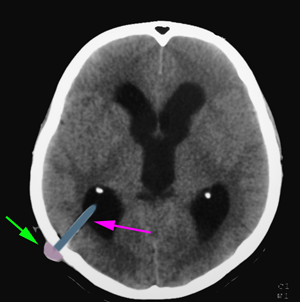

Η κύρια αντένδειξη τοποθέτησης παράκαμψης του Ε.Ν.Υ. είναι η ενεργός λοίμωξη και κυρίως οποιουδήποτε σημείου σχετίζεται με την εμφύτευση του συστήματος (δέρμα, περιτοναϊκή κοιλότητα, οσφύη και Ε.Ν.Υ.). Η οσφυοπεριτοναϊκή παράκαμψη αντενδείκνυται επιπλέον σε αποφρακτικού τύπου υδροκέφαλο. Οι κυριότερες επιπλοκές της τοποθέτησης συστήματος παράκαμψης του Ε.Ν.Υ. είναι η λοίμωξη του συστήματος, η αστοχία του (απόφραξη, ρήξη, μετατόπιση) και η σπανιότερα η αιμορραγία (ενδοεγκεφαλική ή υποσκληρίδιος).